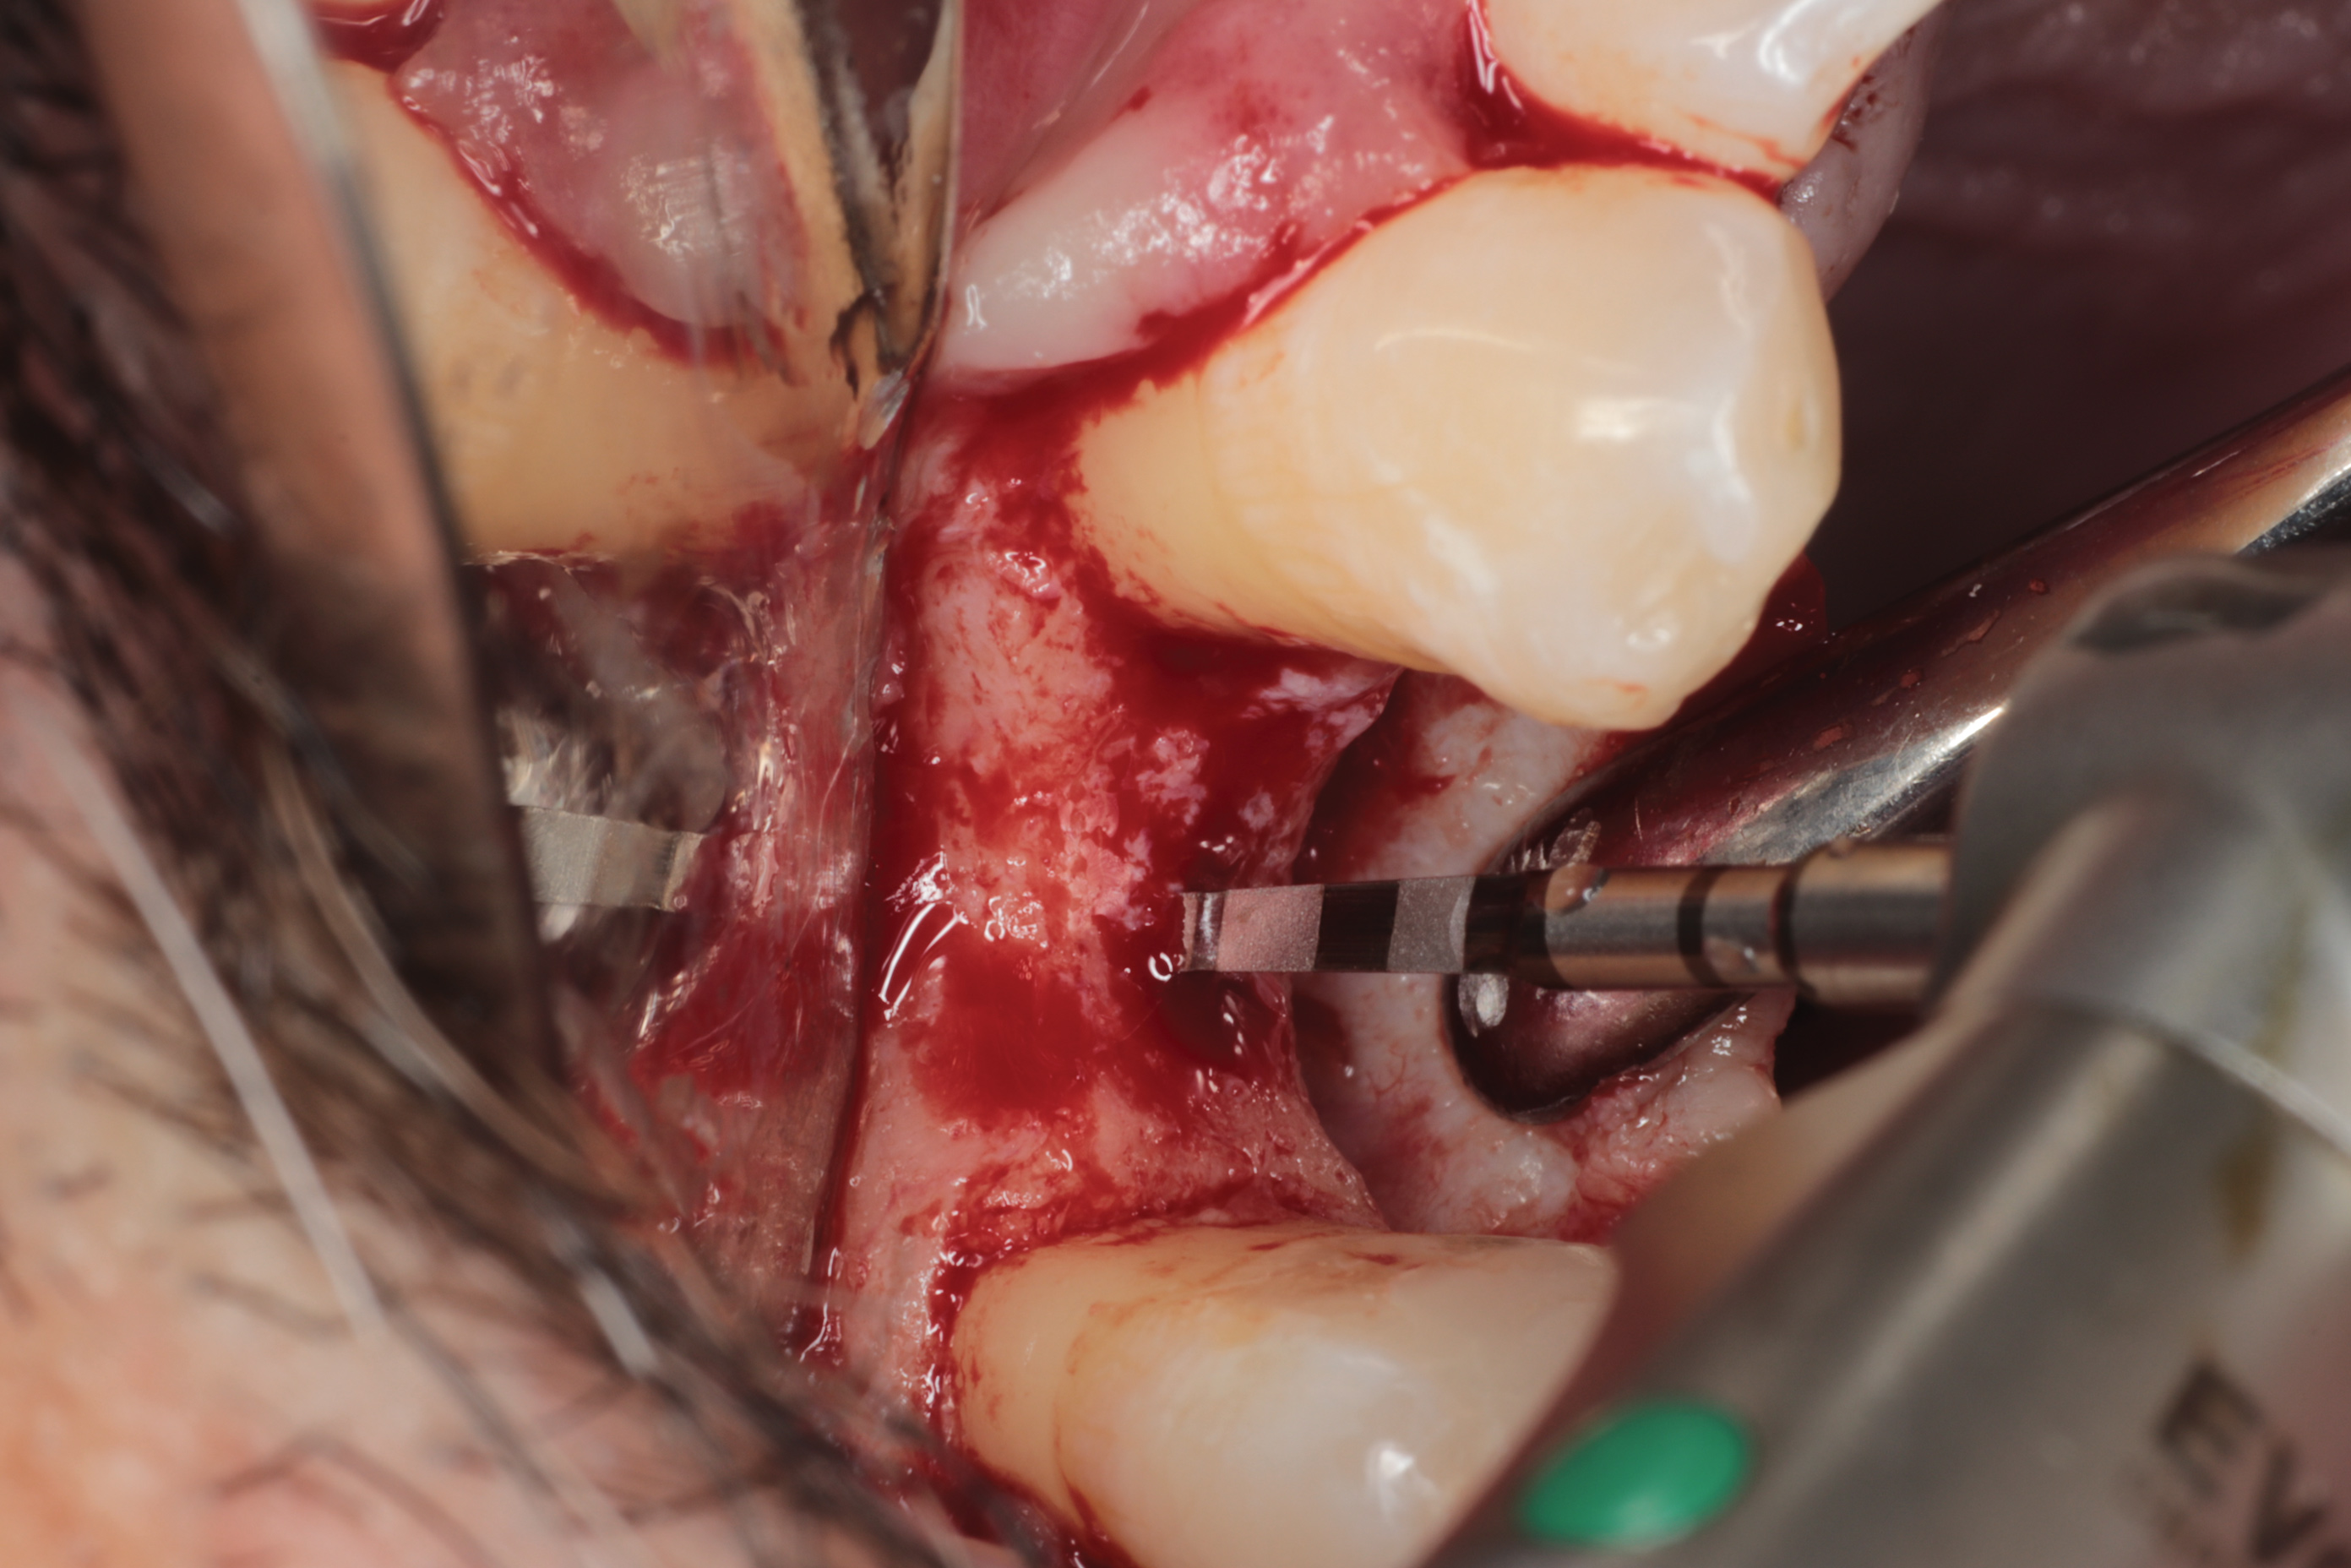

Fig 3. Lateral sinus augmentation; an initial window was created using a combination of a round fissure bur and, as shown, a piezosurgery device tip.

Figure 3

Fig 4. Schneiderian membrane was lifted with the use of a piezosurgery device tip and, as shown, hand instruments.

Figure 4

Fig 6. OD burs were used to create implant osteotomies. OD burs were preferred in this clinical situation to compact the remaining bone by utilizing their counterclockwise rotation, enhancing the densification of bone.

Figure 6